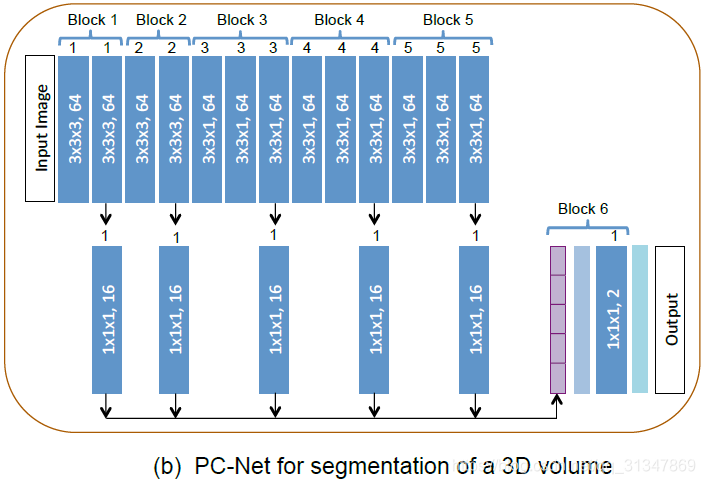

1.2 3D images

对于 3D 图像,需要在感受野、推理时间和存储效率进行 trade-off。

网络结构: 与 P-Net 类似,共有 6 个 block,在第 6 个 block 上进行 fine-tuning等

1)使用各向异性的感受野 85x85x9;

2)采用了 3D context(与之相对的是 slice-based networks);

3)前 2 个 block 使用 3x3x3 的 kernel,第 3、4、5 个 block 使用 3x3x1 的 kernel;

4)为了节省存储空间,在每个 block 的输出下面接一个 1x1x1, 16 的卷积,对输出特征进行压缩之后再进行连接;

5)由于在 P-Net 添加了压缩(compress)操作,所以给处理 3D 图像的网络起名为 PC-Net;